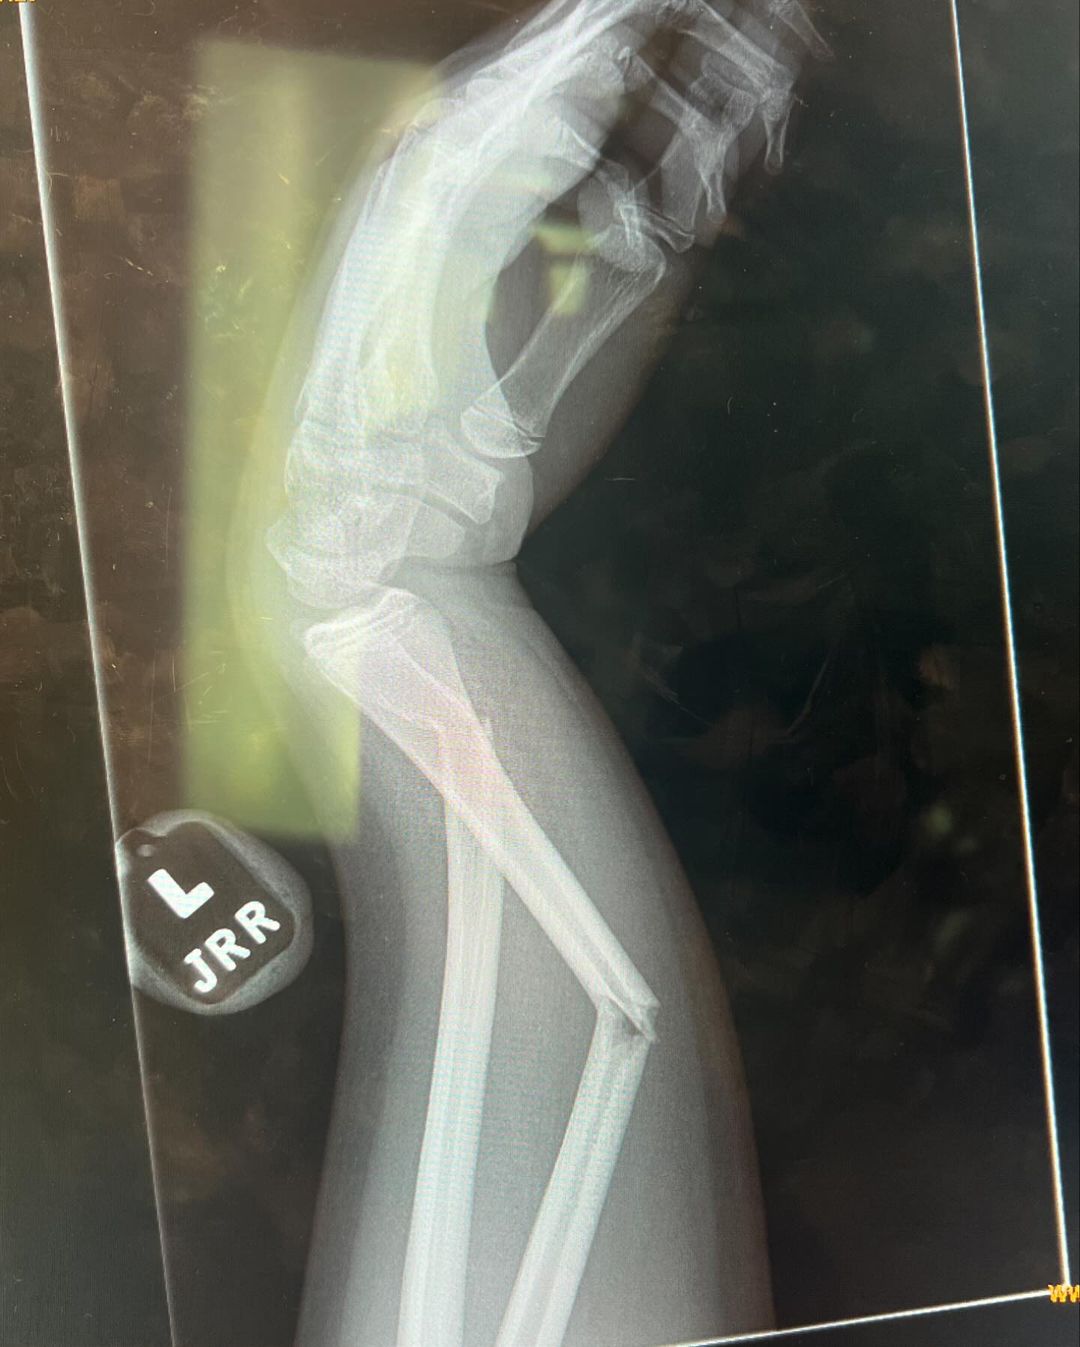

An enlarged X-ray portrait of a broken hand elicited mixed reactions from fans, with some speculating it belonged to Rocky.

Her sister, Khloe, questioned if she had to “post the x-ray,” as a fan added, “Did Kourtney break her arm or one of the kids? Everyone thinks it’s the baby.”

Another fan wrote, “This is a wild x-ray. Hope it heals okay!”

“I hope the baby doesn’t have a fracture… If so, I hope he heals,” a fan penned.

“OMG, I love that car! Hope whoever’s arm that is heals!” another user noted.